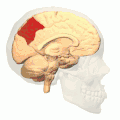

![]() Medial surface of left cerebral hemisphere. (Precuneus visible at top left.) (Anterior to the right.) | |

Precuneus of left cerebral hemisphere (shown in red). -

Medial surface of left cerebral hemisphere. (Precuneus visible at top left.) -

Medial surface of left cerebral hemisphere. (Precuneus colored in red.)